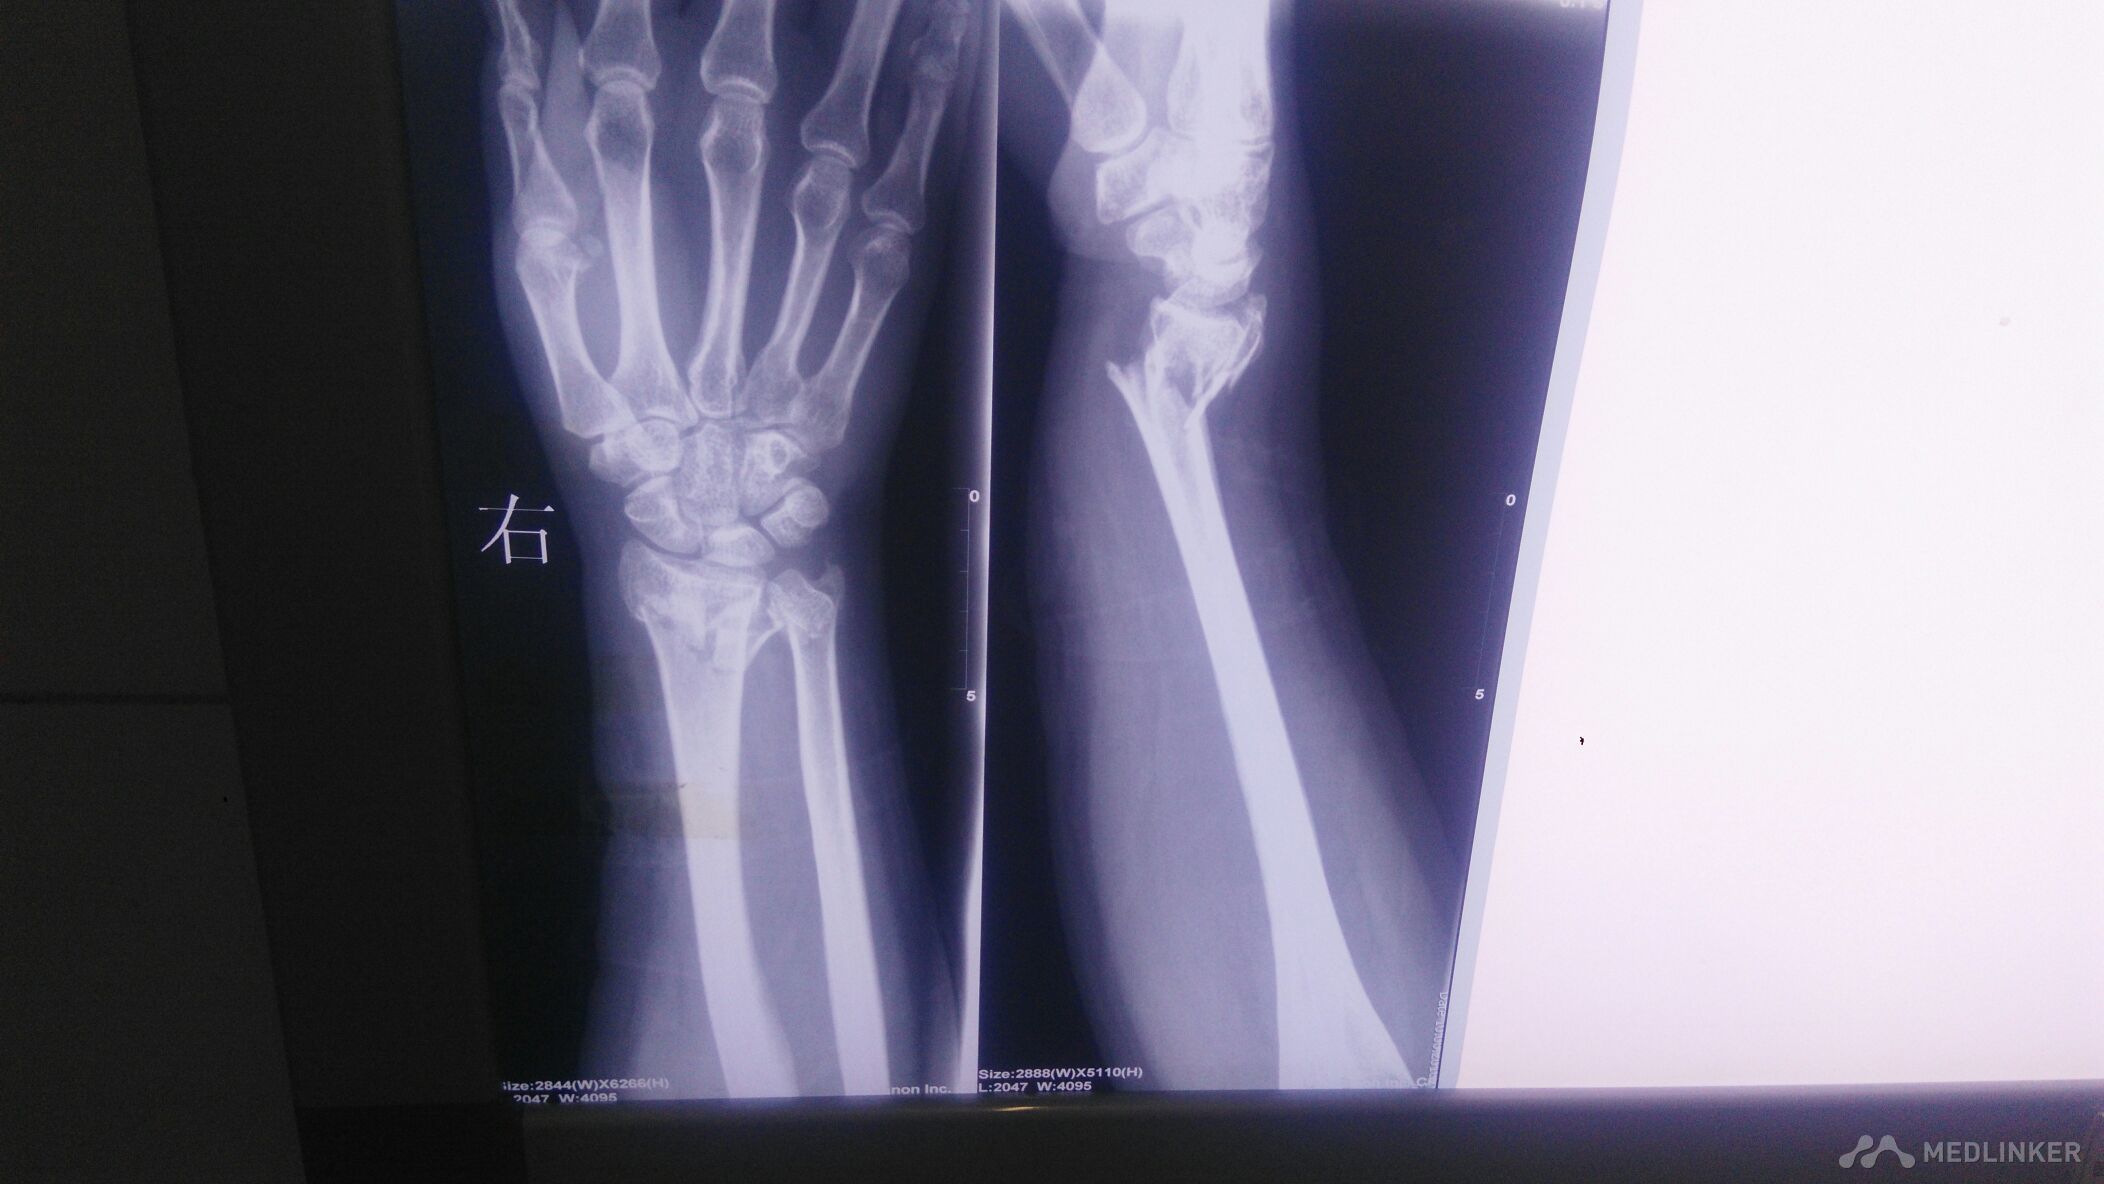

右腕部外伤后,畸形明显,肿胀明显。右腕部感觉麻木。活动受限。

右腕部以桡骨远端处,尺骨远端处压痛阳性,叩痛阳性,右手血运可。末梢冰冷。

右侧桡骨远端粉碎性骨折,右侧尺骨远端骨折,保守治疗。